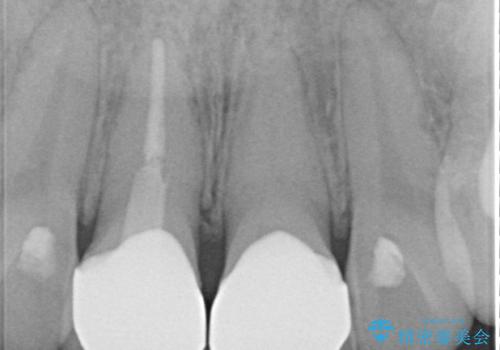

- 神経を取り除いた後に歯の色が変色して気になってきたとのことで来院された患者様です。

前歯は片側のみ神経を取り除かれていましたが、反対側もむし歯治療の詰め物が広範囲に及んでいたため、両方の歯をオールセラミッククラウンにて補綴治療を行うこととしました。

奥歯も著しく茶色に変色していたため、同様にオールセラミッククラウンにて補綴治療を行うこととしました。